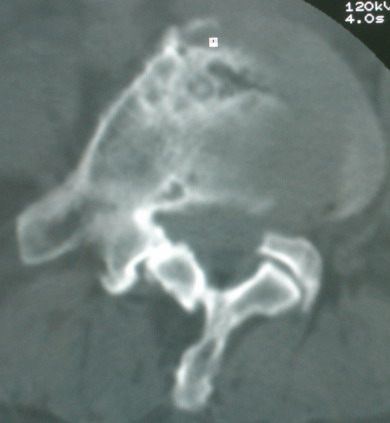

以下是引用卜一在2008-6-3 19:33:00的发言:[br]双肺结节,以双上肺分布为多,期间搀杂片状致密影及索条致密影。考虑:继发性肺结核伴血型播散可能性大。不除外肺泡ca的可能!另:椎体退变!

以下是引用panyishengct在2008-6-3 21:09:00的发言:[br]双上肺弥漫性小结节影,纵隔窗内钙化淋巴结影,考虑矽肺或/和tb可能性较大,不除外肺ca可能。腰椎考虑退变。 [br][br]